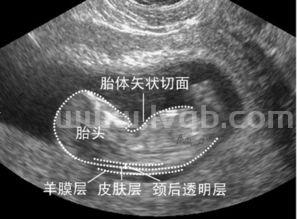

NT检查是通过B超检查来评估胎儿是否患有唐氏综合征,在怀孕11-14周左右检查,去正规的大医院进行B超检查,检查结果相对准确。NT检查有范围,如果大于5mm可能胎儿发育异常,要进一步检查,比如可以做羊水穿刺、无创DNA等。

nt检查由于医院级别不同,地域不同,医院的收费标准也有所不同,一般来说费用在几百元左右。nt检查可以早期诊断胎儿染色体疾病和早期发现多种原因造成的胎儿异常,一般在怀孕11周~14周之间做。